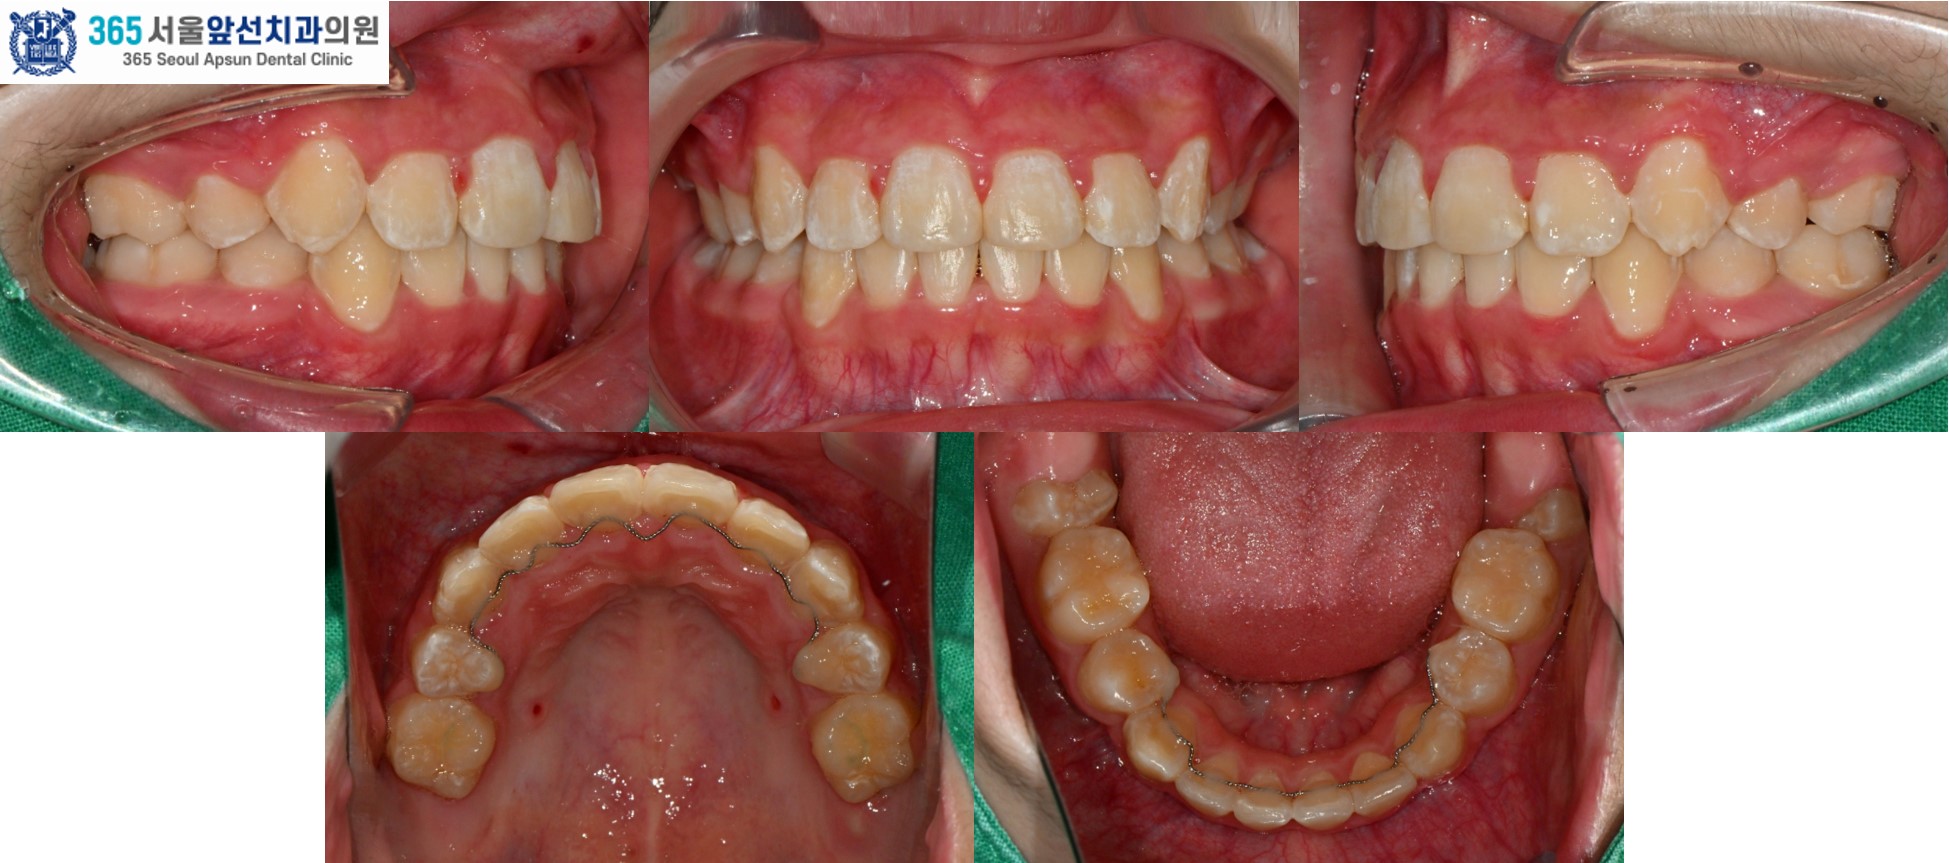

돌출입과 덧니를 고민으로 내원하신, 10대 청소년 환자 분의 증례를 소개드리겠습니다. 촬영일시 : 2024.05.21. / 2026.03.28 치료 전, 심한 공간 부족으로 송곳니 덧니와 앞니의 비뚤비뚤하게 겹친 치열이 관찰됩니다. 상악 치열의 경우 7.0mm의 공간 부족, 하악 8.5mm의 공간 부족이 있습니다. 임상적 및 방사선학적 검사 결과 위턱의 돌출과 아래턱의 후퇴를 동반한 2급 골격과, Angle씨 분류 치성 2급 부정교합 및 과도한 수직 및 수평 피개(과개교합)과 심한 총생으로 진단되었습니다. 치아 크기에 비해 악궁의 크기가 작은 부조화도 있으셔서, 비발치 교정보다는 발치 교정으로 치료하는 것이 적합합니다. 따라서, #14,24,34,44 제1소구치 치아의 발치와 전체 치열의 고정식 교정장치 치료(Clippy-C), 상악 교정용 미니임플란트를 이용한 추가적 치열의 후방이동을 계획하였습니다. 촬영일시 : 2024.05.21. 치료 후의 모습입니다. 2024년 6월 5일 치료를 개시하여 2026년 3월 28일에 교정치료를 종료하였으며 총 1년 8개월의 치료기간이 소요되었습니다. 치열이 가지런하게 배열되면서 후방이동 되어 Angle씨 분류 치성 1급 관계가 달성되었고, 얼굴형 또한 돌출입의 개선과 더불어 입술 폐쇄가 개선되었습니다.

촬영일시 : 2024.05.21. / 2026.03.28. [ 치료기간: 2024년 5월 21일 ~2026년 3월 28일 )] |